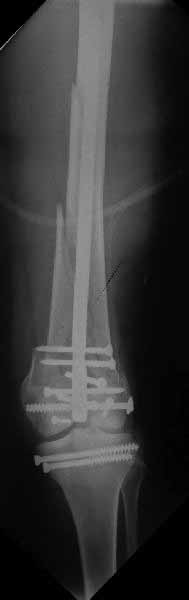

Ответ на эту часть Вашего поста – вложенный файл. Больная оперирована неделю назад по поводу открытого перелома дистального эпиметафиза бедренной кости. После операции она идёт в рентгенкабинет для выполнения послеоперационной контрольной рентгенографии, представленной на слайдах 10 и 11. Узнав, почему её фотографируют, просила передать Вам, Антон, привет.

В приложении пример недавней операции, C3, открытая репозиция, фиксация мыщелков спицами и винтами, ретроградный синтез большеберцовым гвоздем 10,5 мм диаметром, винты 5 мм.

Позволю себе напомнить коллегам ещё раз, что являюсь сторонником антеградного остеосинтеза при переломах дистального эпиметафиза бедренной кости. Такая приверженность основана не на преимуществах внесуставного введения стержня или большем проценте положительных результатов. Она основана на возможности обеспечить блокирование на минимальном расстоянии от суставной поверхности в нескомпрометированной кости и, таким образом стабилизировать максимально низкие переломы. В приведенном Вами случае самый дистальный из блокирующих винтов проведен на расстоянии более 2 см от конца стержня. Из-за того, что к стержню присоединяется кондуктор, на стержне теряется 1-1,5 см его длины, где можно было разместить отверстия для блокирования. И что более важно, вместе с потерянной для этой цели длиной стержня утрачивается для размещения блокировочных винтов, пожалуй, самая ценная часть дистального эпиметафиза бедренной кости. Проблемы дистального блокирования в разных плоскостях, локализации точки ввода стержня при антеградном остеосинтезе – это всё решаемые технические проблемы. Но антеградный остеосинтез низких дистальных переломов бедра при адекватном блокировании в нескомпрометированной кости обеспечивает решение стратегической задачи – стабильный остеосинтез и возможность нагрузки.